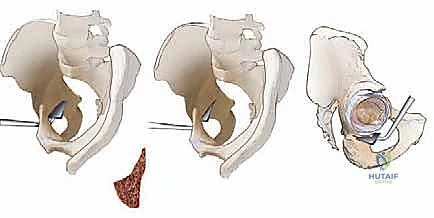

الخطوة الثالثة: القطع العظمي المتعدد (The Osteotomies)

هنا تكمن عبقرية الجراحة. يقوم الدكتور هطيف بإجراء سلسلة من القطوعات العظمية الدقيقة باستخدام أزاميل ومناشير جراحية متخصصة:

1. قطع عظمة الإسك (Ischial Cut): الجزء السفلي والخلفي من الحوض.

2. قطع عظمة العانة (Pubic Cut): الجزء الأمامي من الحوض.

3. قطع عظمة الحرقفة (Iliac Cut): الجزء العلوي من الحوض.

هذه القطوعات تحرر تجويف الحُق بالكامل عن باقي الحوض، مع الإبقاء على الحلقة الحوضية الخلفية سليمة لضمان استقرار الحوض أثناء المشي بعد العملية.

الخطوة الخامسة: التثبيت (Fixation)

بمجرد الوصول إلى الوضع المثالي، يتم تثبيت التجويف في مكانه الجديد باستخدام مسامير طبية (Screws) مصنوعة من التيتانيوم أو الفولاذ المقاوم للصدأ. هذه المسامير تمسك العظم بقوة حتى يلتئم العظم المقطوع بمرور الوقت (عادة خلال 6 إلى 8 أسابيع).